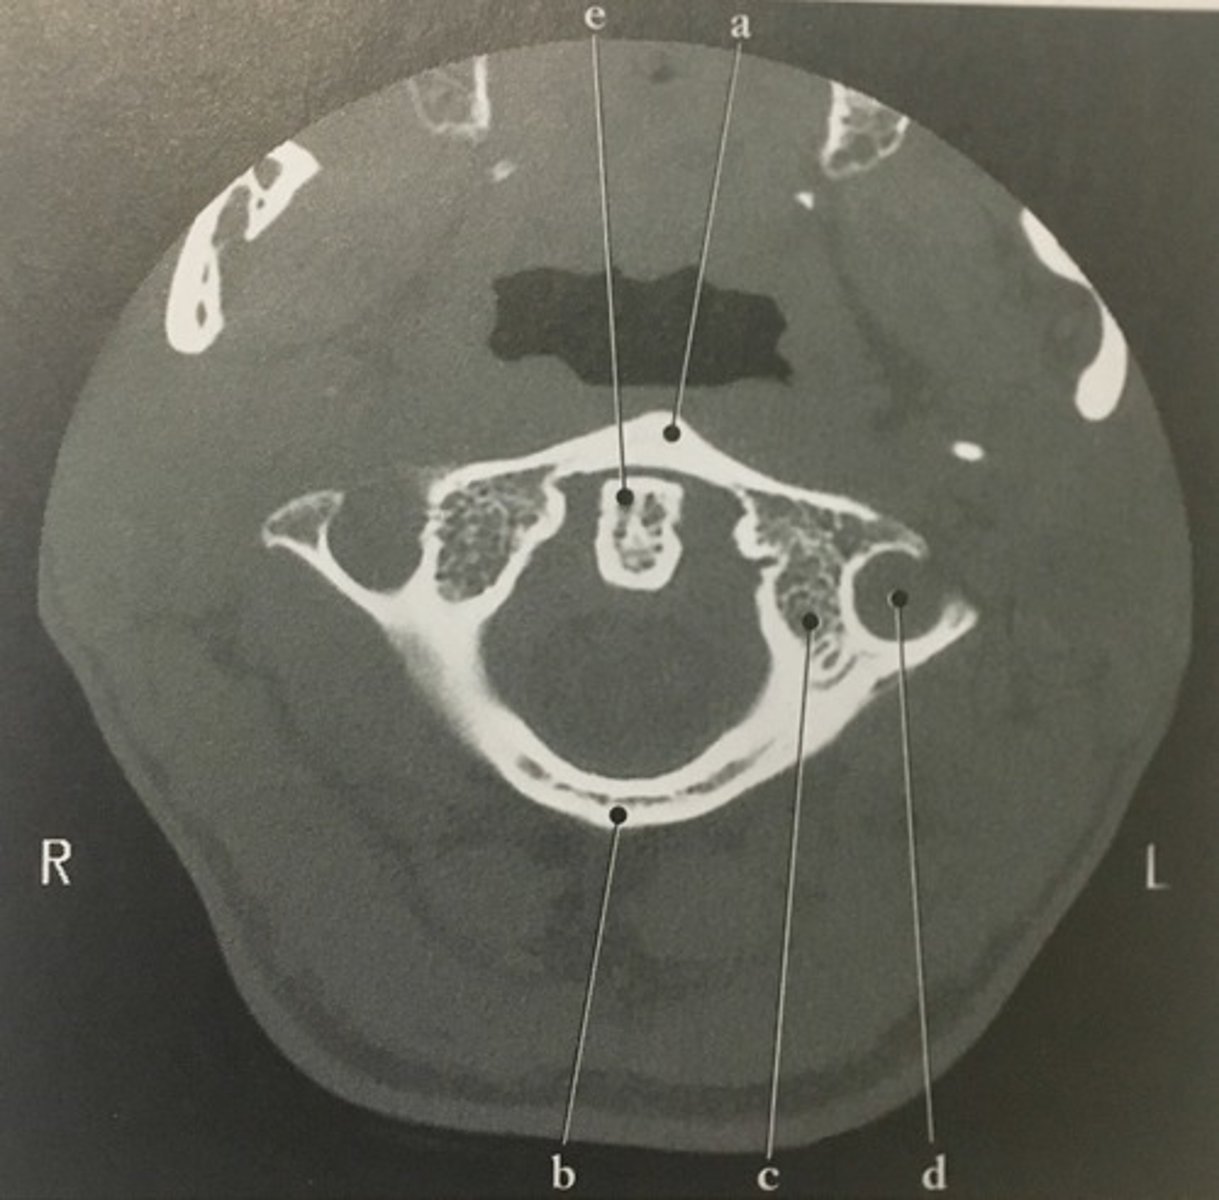

Identify structure A on this axial CT slice of the C1.

<p>Identify structure A on this axial CT slice of the C1.</p>

99

Posterior arch

Identify structure B on this axial CT slice of the C1.

<p>Identify structure B on this axial CT slice of the C1.</p>

New cards

Lateral mass

Identify structure C on this axial CT slice of the C1.

<p>Identify structure C on this axial CT slice of the C1.</p>